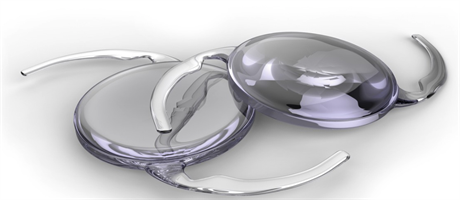

En Premiumlins är en lins som inte bara ersätter den egna linsen, utan som även har refraktiva egenskaper, dvs korrigerar synfel. Syftet är att minska glasögonberoendet.

Premiumlinser eller Refraktiva linser finns i olika utföranden.

Teknologin kring premiumlinser utveckas kontinuerligt. De premiumlinser som vi erbjuder är av senaste slag. Vi använder även den senaste teknologin för de omfattande mätningar som görs innan operationen och i samband med ingreppet.